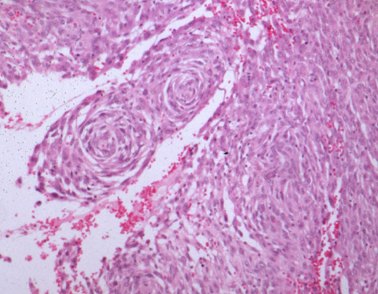

How do haemangiopericytomas present histologically?

Perivascular whorls of fusiform cells

Low metastatic potential

Centre of whorls = vessel